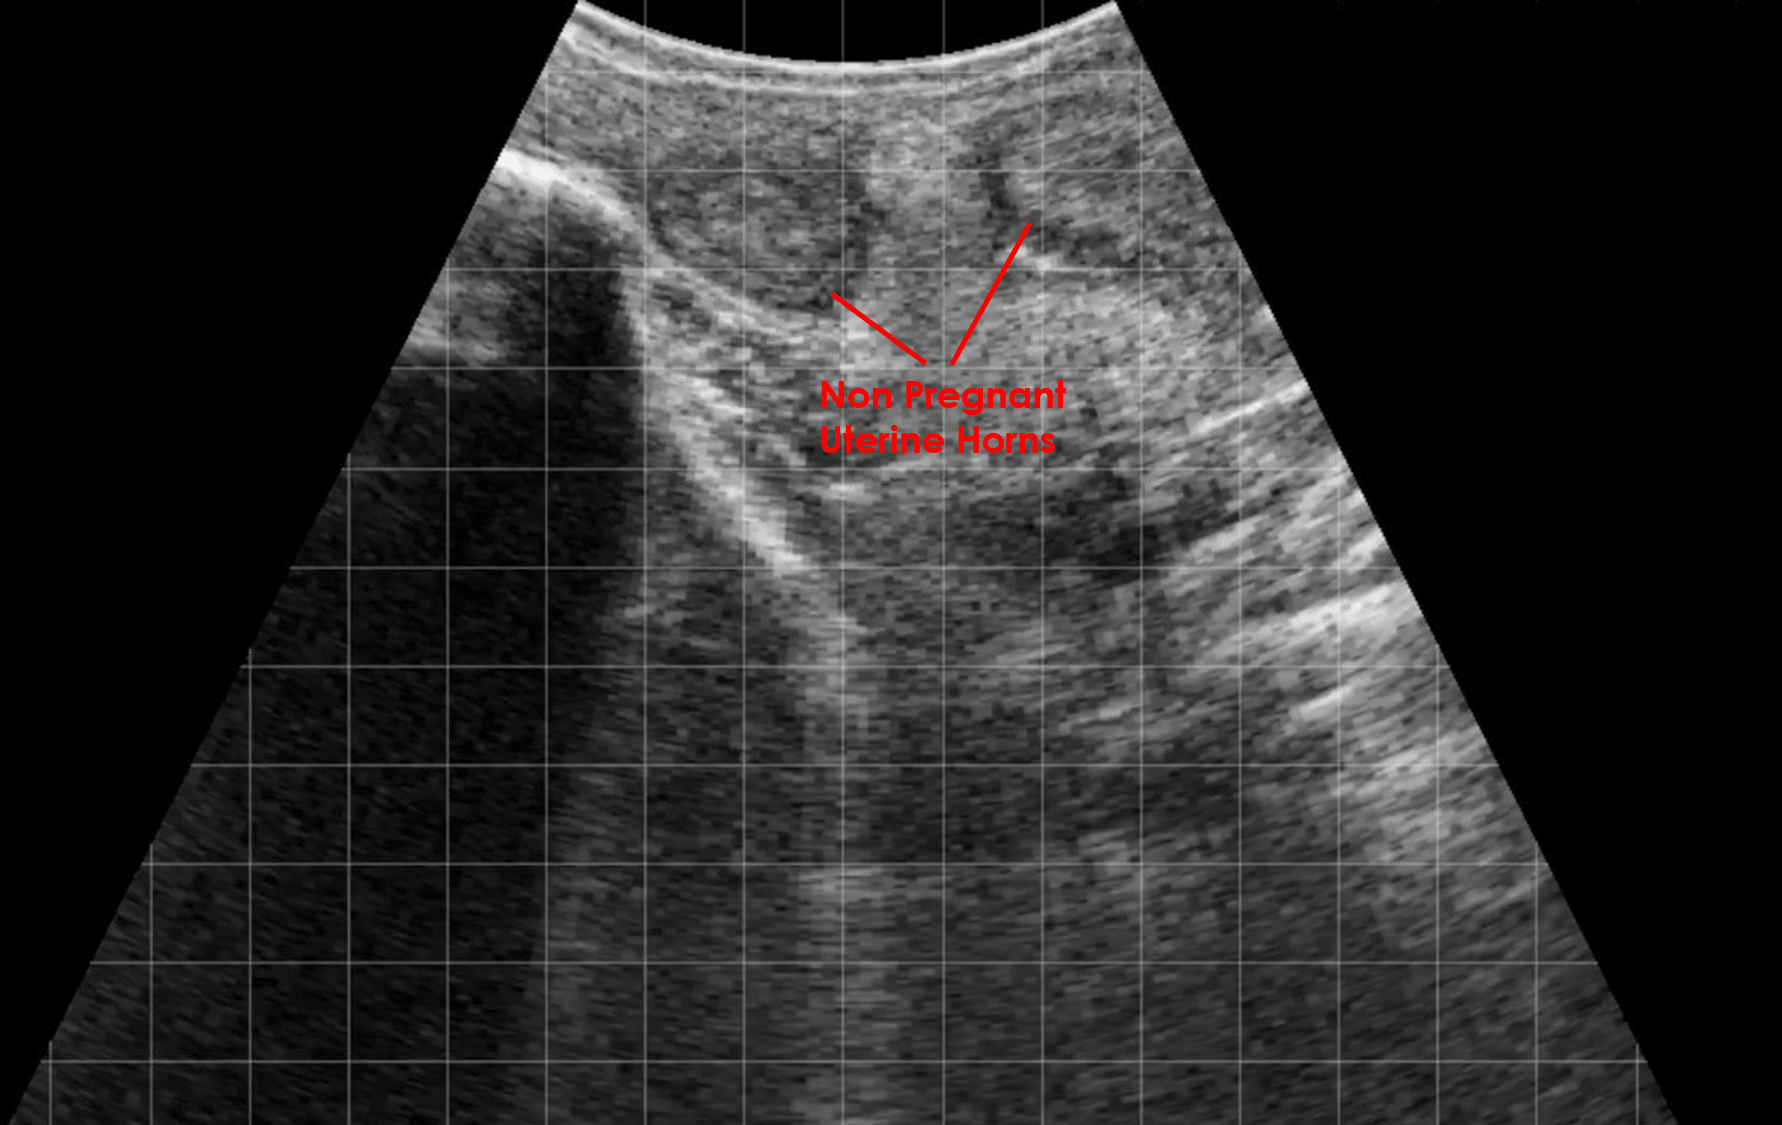

Nonpregnant uterine horns bovine EasiScanGo curve IMV imaging

From www.imv-imaging.com

Nonpregnant uterine horns bovine EasiScanGo curve IMV imaging Single Horn Uterus Unicornuate uterus is a rare genetic condition in which only one half of a girl’s uterus forms. A unicornuate uterus or unicornis unicollis is a type of müllerian duct anomaly (class ii). This is why the condition is. As a result, you may have a. Usually this disorder isn't detected until. A unicornuate uterus is smaller than a typical. A. Single Horn Uterus.